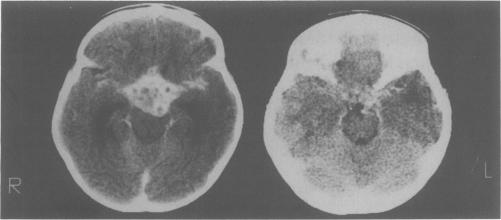

A 5 year old girl with tuberculous meningitis developed progressive visual failure during in-patient anti-tuberculous chemotherapy due to an ophthochiasmatic tuberculoma. This was successfully managed by prolonged high-dose corticosteroids and continued anti-tuberculous therapy resulting in complete visual and psychosocial recovery.

https://cdn.ncbi.nlm.nih.gov/pmc/blobs/bae5/2399604/c7b3459b425e/postmedj00050-0067-a.jpg